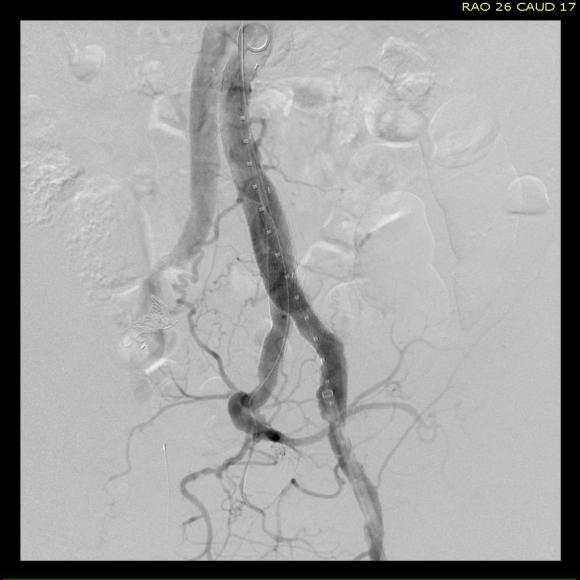

For example, take this patient who after EVAR of aortic aneurysm with AFX developed metachronous dilatation of the common iliac artery to 3.9cm with abdominal pain. The average diameter is 18.5mm. From the table, that rounds to 19mm corresponding to 283.53 square mm. If the internal iliac artery requires a 13mm graft, that is 132.73 square mm, the difference being 150.80 square mm. That corresponds to a 14mm diameter graft, but a slightly larger graft is preferred for oversizing. The external iliac artery is 8mm, and putting a 13mm Viabahn (largest available) in that would result in the B-infolding in the 8mm external iliac. Here, I bailed myself out by simply placing a 20mm AFX iliac limb extension, which by virtue of its design is resistent to infolding and tolerant of parallel grafts laid alongside in constricted channels. I found that the AFX iliac limb, a 20-13mm x 88mm length extension well suited for this.

The AFX graft limb seems to adapt to the presence of the parallel “sandwich” graft which is deployed second and ballooned last. In followup, there was shrinkage of the common iliac artery aneurysm sac and no endoleak.

Compared to my other parallel graft case treating a metachronous saccular common iliac aneurysm years after an EVAR with a Gore endograft (link), which by table calculation, resulted in 8% oversize in calculated areas, this particular technique with a large AFX graft and an appropriately sized Viabahn seemed to work well the setting of a previously placed AFX graft. It allows one to avoid hypogastric occlusion.